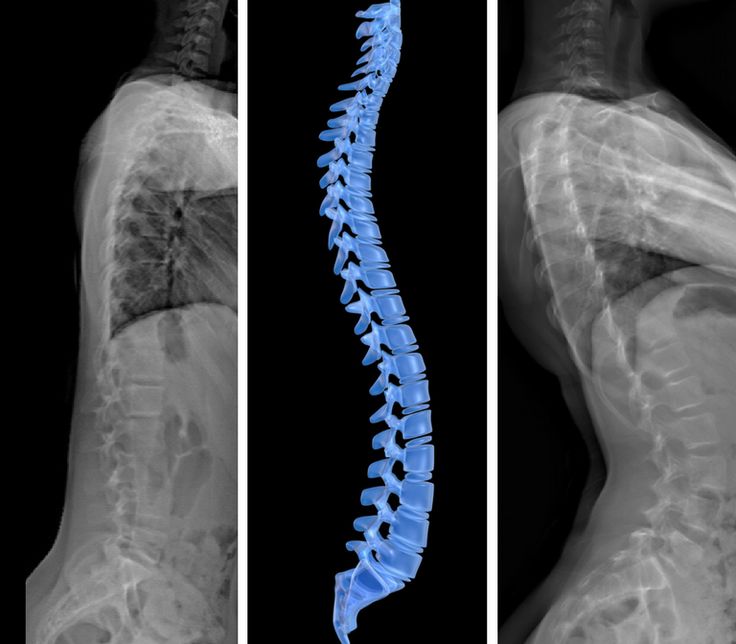

Bel Fıtığı Emarda Belli Olur Mu?

Hastaların en çok merak ettiği sorulardan biri de bel fıtığı emarda belli olur mu sorusudur. Bu konudaki cevap oldukça nettir: Evet, belli olur. MR sayesinde:

- Omurların arasındaki disklerin yapısı detaylı şekilde incelenir.

- Diskin sinir köklerine baskı yapıp yapmadığı anlaşılır.

- Fıtığın derecesi ve boyutu net biçimde görülür.

Bu nedenle bel fıtığının teşhisinde MR altın standarttır. Röntgen ya da tomografi bazı bilgileri verse de yumuşak dokuları en net şekilde MR gösterir.

Bel Fıtığı MR Raporunda Ne Yazar?

Çekim sonrası hazırlanan MR raporu, uzman doktorlar tarafından değerlendirilir. Raporda genellikle şu bilgiler yer alır:

- Disklerdeki dejenerasyon (yıpranma) bulguları.

- Fıtığın yerleşim yeri (L4-L5, L5-S1 gibi seviyeler).

- Sinir köklerine bası olup olmadığı.

- Spinal kanalda daralma (spinal stenoz) bulguları.

Bel fıtığı mr raporu, doktorun hastaya en doğru tedavi planını yapabilmesi için oldukça önemlidir.